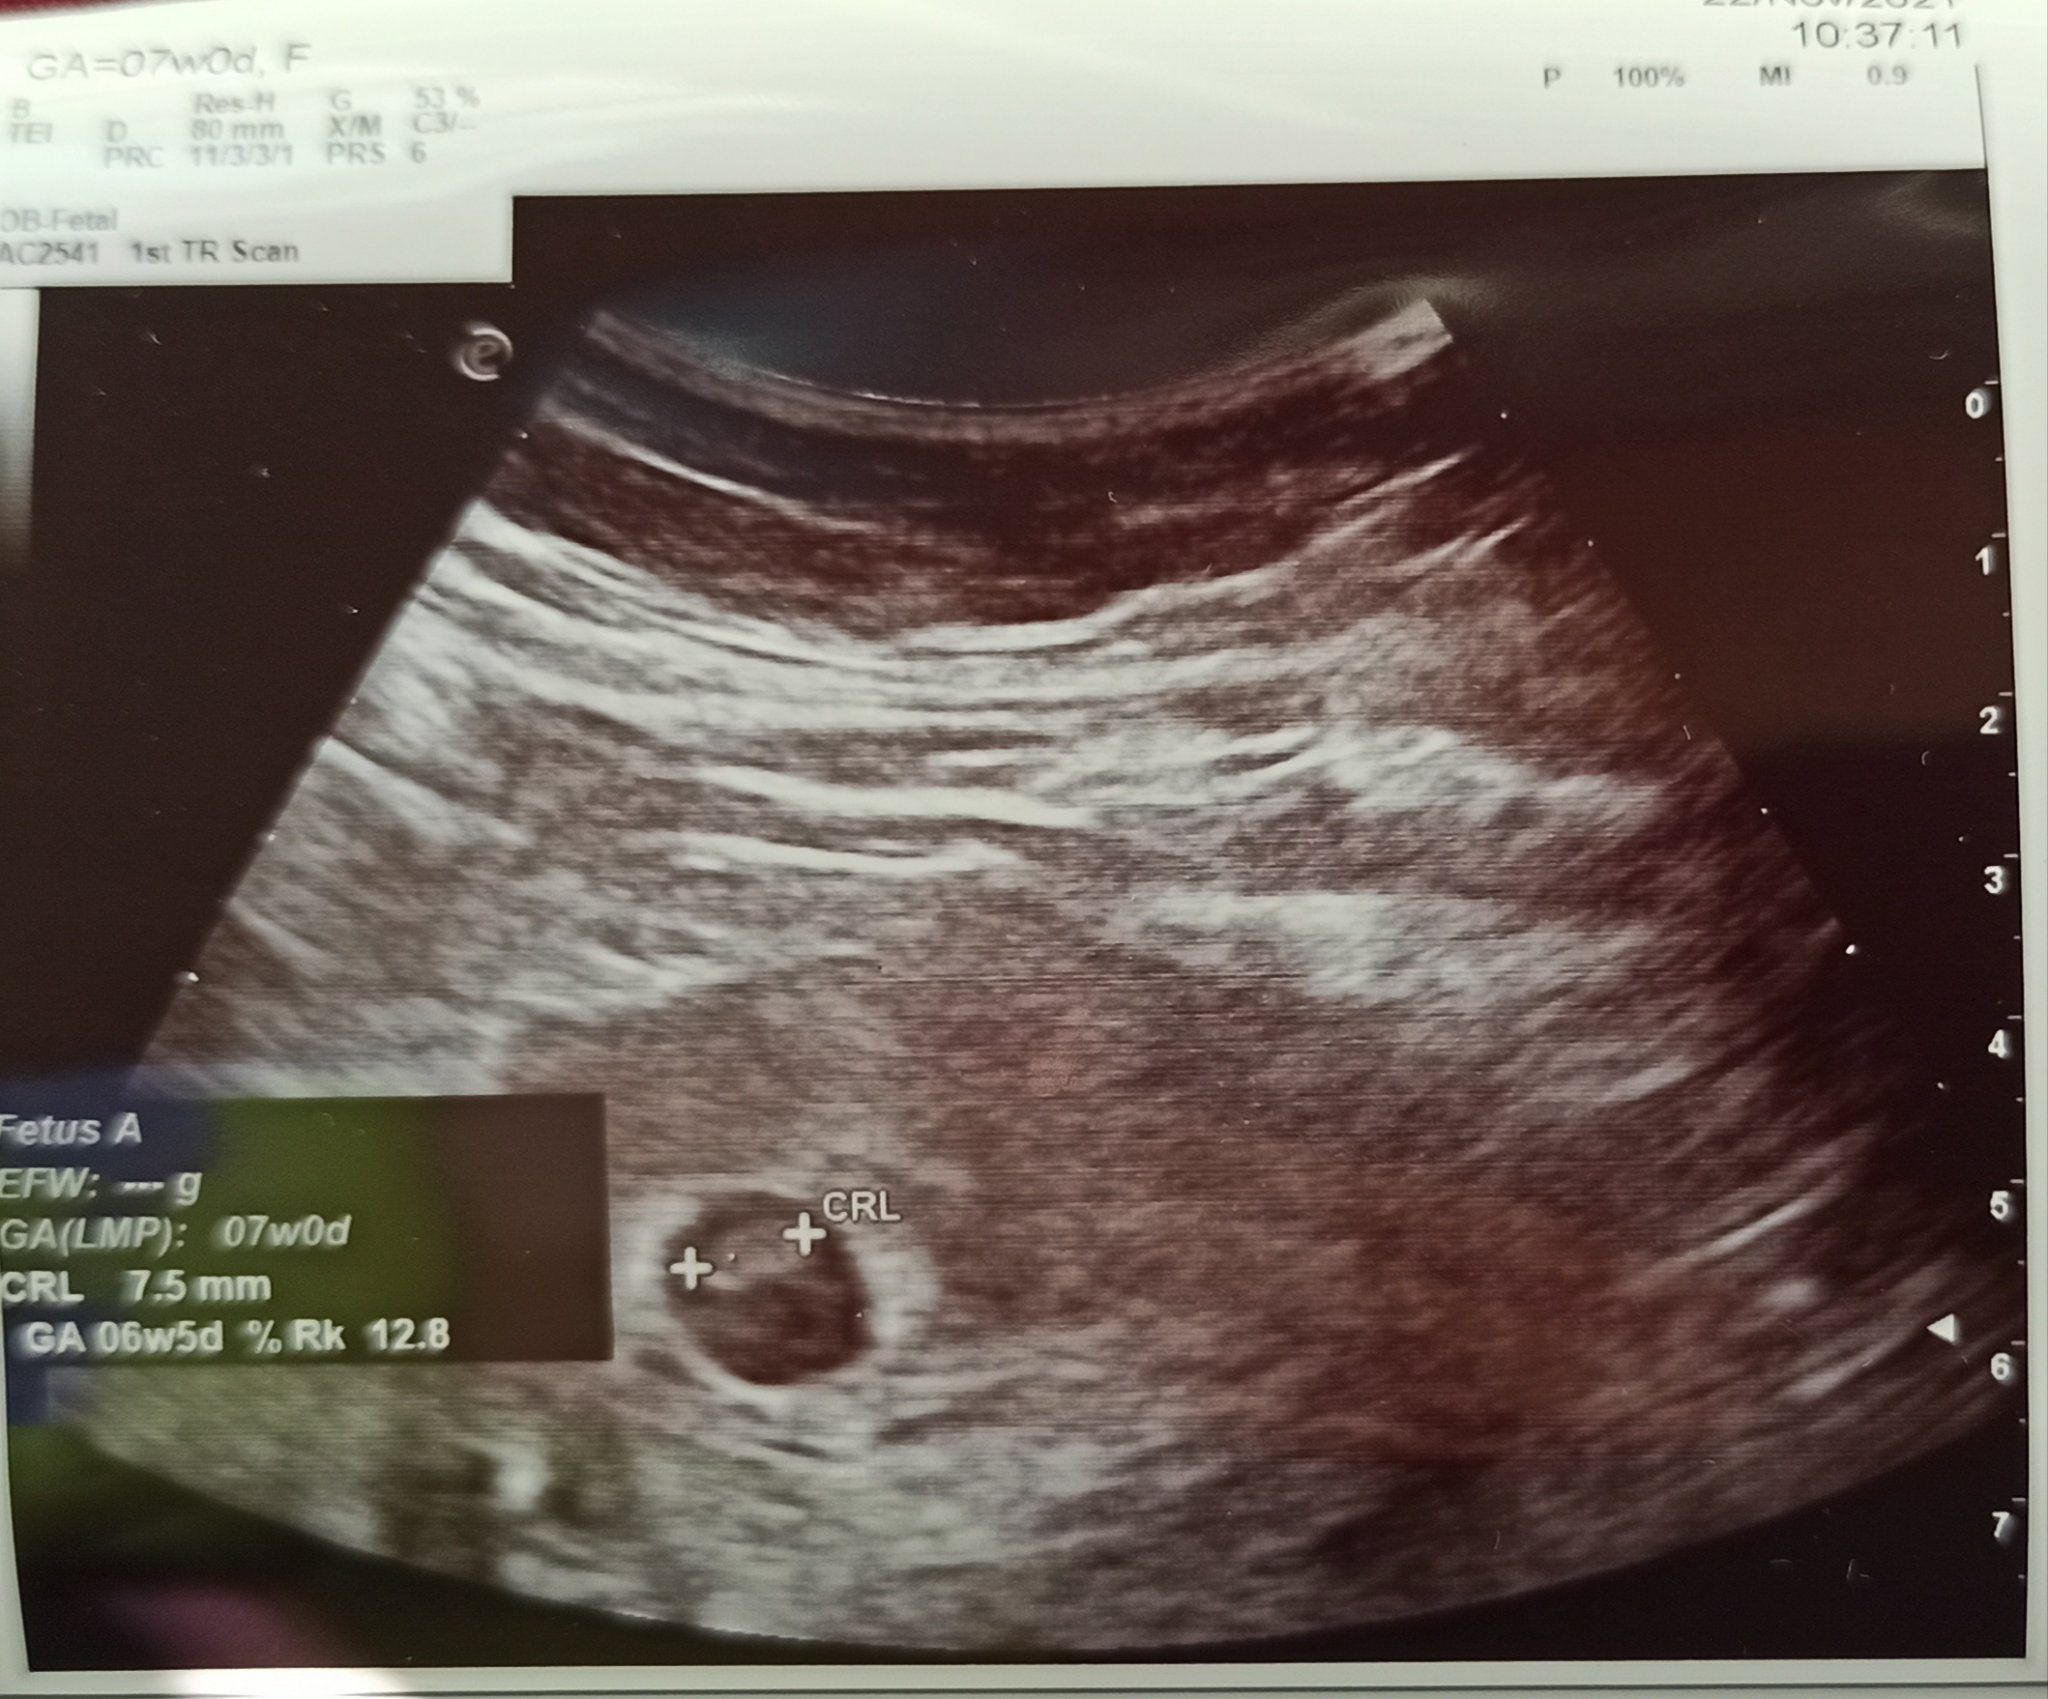

Как мога да определя датата на термина, когато цикълът ми е нередовен?